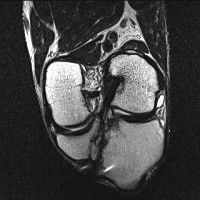

무릎 mri 간단히 봐주실 수 있으시나요 ㅠㅠ

안녕하세요 8년전 십자인대 수술하고 최근 무리한 운동에 무릎 불편감이 생겨서

mri 찍었습니다.

진단결과는 첫 찍은 병원에서 활액막염 이라는 진단을 받았습니다. 혹시 봐주실 수 있으실까요?

진단결과가 달라 혼란스럽습니다 ㅠㅠ

• 안녕하세요. 강성주 의사입니다.

올라온 MRI가 단편적이라서 정확한 진단에 어려움이 있지만 십자인대에는 큰 이상이 있지는 않은것 같으며, 무릎관절내 물이 있는 것으로 보아 활액막염의 진단이 맞을 것 같습니다.

하지만 단편적인 영상이기 때문에 촬영병원에서 정확한 판독지 등을 받으시는 것이 좋겠습니다.